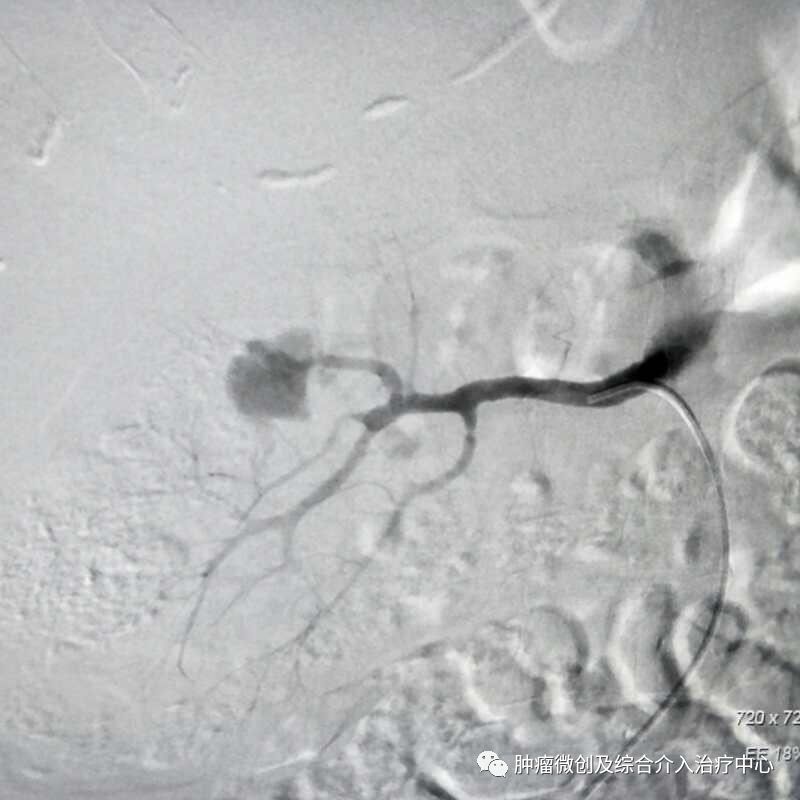

(鼻咽癌颈部转移瘤破溃出血,DSA造影提示左颈部病变血管迂曲、紊乱,内有出血)